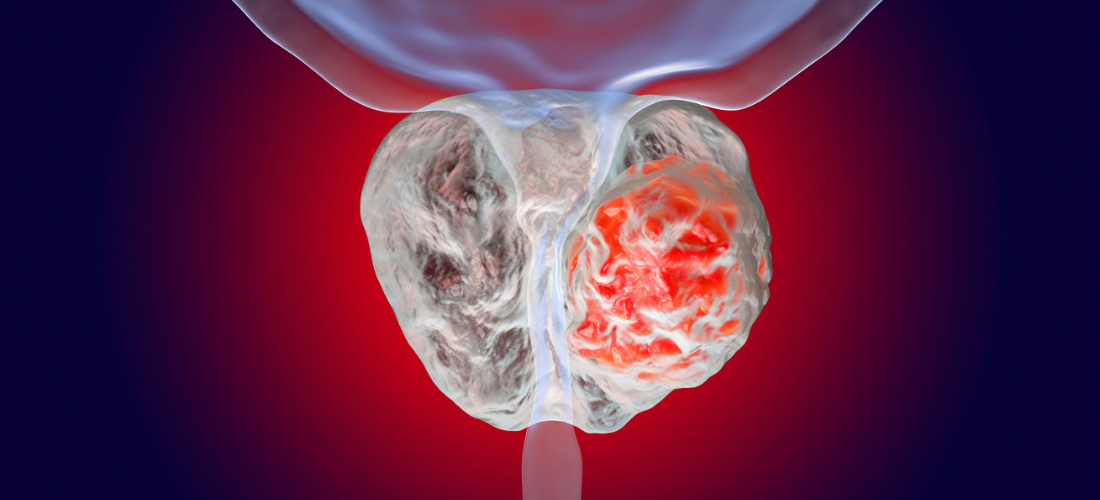

Опухоль аденомы простаты симптомы. Раковые заболевания простаты. Раковая опухоль простаты. Предстательная железа у мужчин онкология Злокачественная опухоль простаты. Злокачественное новообразование предстательной железы. Злокачественные новообразования простаты

Злокачественная опухоль простаты. Злокачественное новообразование предстательной железы. Злокачественные новообразования простаты Карцинома предстательной железы. Злокачественное новообразование предстательной железы. Cancer предстательной железы. Аденома предстательной железы – это опухоль

Карцинома предстательной железы. Злокачественное новообразование предстательной железы. Cancer предстательной железы. Аденома предстательной железы – это опухоль Предстательная железа, Prostata. Аденома предстательной железы. Карцинома предстательной железы. Злокачественное новообразование предстательной железы

Предстательная железа, Prostata. Аденома предстательной железы. Карцинома предстательной железы. Злокачественное новообразование предстательной железы Cancer предстательной железы. Аденокарцинома предстательной железы. Онкология предстательной железы

Cancer предстательной железы. Аденокарцинома предстательной железы. Онкология предстательной железы Опухоль предстательной железы у мужчин. Злокачественное новообразование предстательной железы. Эктопия предстательной железы. Карцинома предстательной железы

Опухоль предстательной железы у мужчин. Злокачественное новообразование предстательной железы. Эктопия предстательной железы. Карцинома предстательной железы